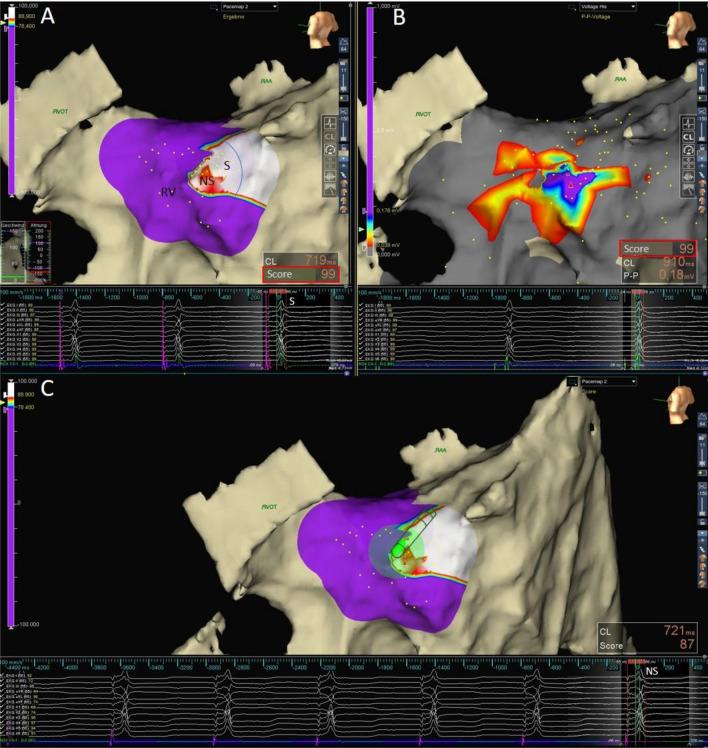

Pace mapping and visual comparison of the local pacing response with the intrinsic QRS morphology form the mainstay of His bundle pacing (HBP). We evaluated the performance of a surface lead morphology match algorithm for automated classification of the pacing response in patients with narrow intrinsic QRS undergoing electroanatomic mapping (EAM)-guided HBP. HBP was attempted in 43 patients. In 28 cases with narrow QRS, the EnSite AutoMap Module was used for automated assessment of the QRS morphology resulting from pace mapping in the His cloud area with either a diagnostic catheter or the His lead. An intrinsic morphology match score (IMS) was calculated for 1.546 QRS complexes and assessed regarding its accuracy and performance in classifying the individual pacing response as either selective HBP (S-HBP), nonselective HBP (NS-HBP) or right ventricular stimulation. Automated morphology comparison of 354 intrinsic beats with the individual reference determined a test accuracy of 99% (95% CI 98.96-99.04) and a precision of 97.99-99.5%. For His-lead stimulation, an IMS ≥ 89% identified S-HBP with a sensitivity, specificity and positive predictive value of 1.00 (0.99, 1.00) and a negative predictive value of 0.99 (0.98, 1.00). An IMS between 78 and < 89% indicated NS-HBP with a sensitivity and specificity of 1.00 (0.99, 1.00) and 0.99 (0.98, 1.00), respectively. IMS represents a new automated measure for standardized individual morphology classification in patients with normal QRS undergoing EAM-guided HBP.Clinical trial registration: NCT04416958.